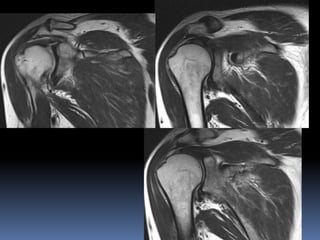

 Recurrent Dislocation shoulder

Anterior middle posterior

Coronal sections

Posterior sections of shoulder